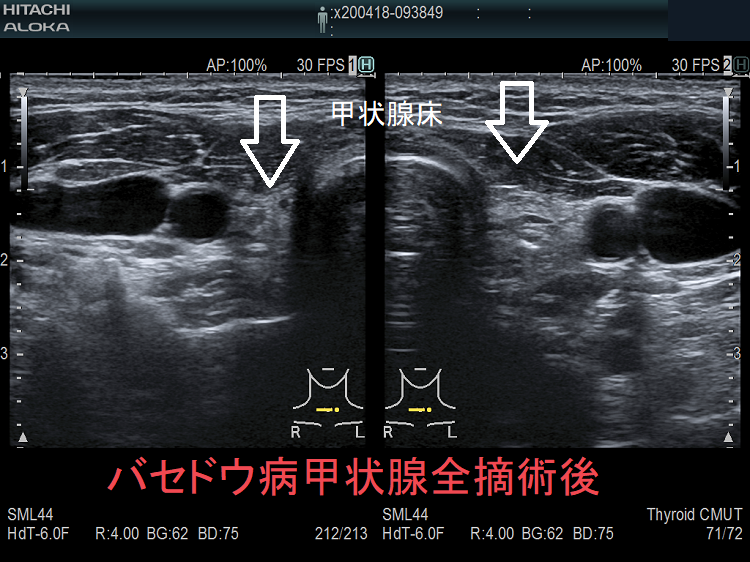

- 甲状腺摘術後、TSH 抑制療法;バセドウ病/甲状腺腫瘍で甲状腺切除と同時に副甲状腺も取ってしまった場合、取らずに温存した場合でも副甲状腺への血管を傷つけた場合

- 甲状腺全摘術時、副甲状腺も1-4腺を同時切除、あるいは切除しなくても栄養血管を損傷

- 甲状腺亜全摘術時、副甲状腺を数腺温存したつもりが、栄養血管を損傷

すると、

- 術後副甲状腺機能低下症による低カルシウム血症;術直後のみならず、10年~30年以上して著明な低カルシウム血症で発症する事もある(日腎会誌 2012;54(1):40-47.)(J Clin Diagn Res. 2017 Feb; 11(2): OD07–OD09.)。